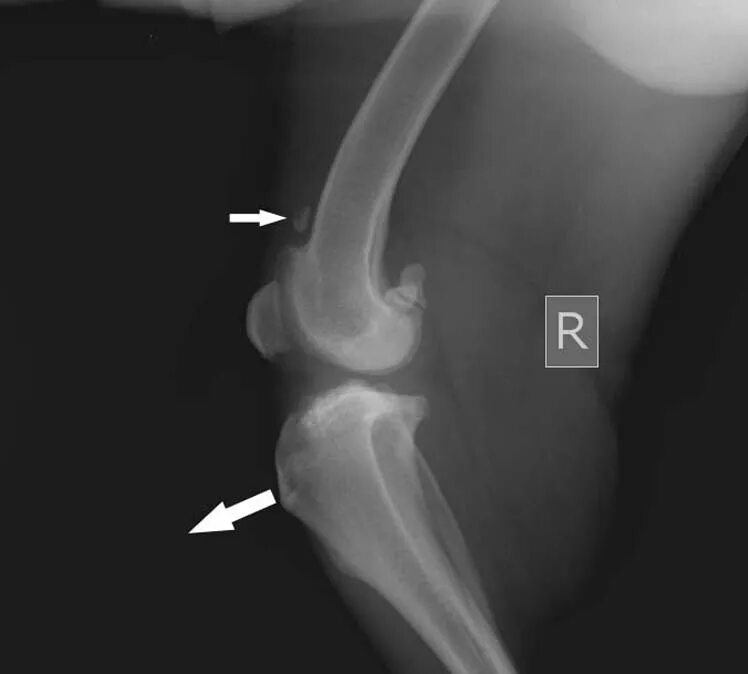

Обызвествление сухожилий мышц